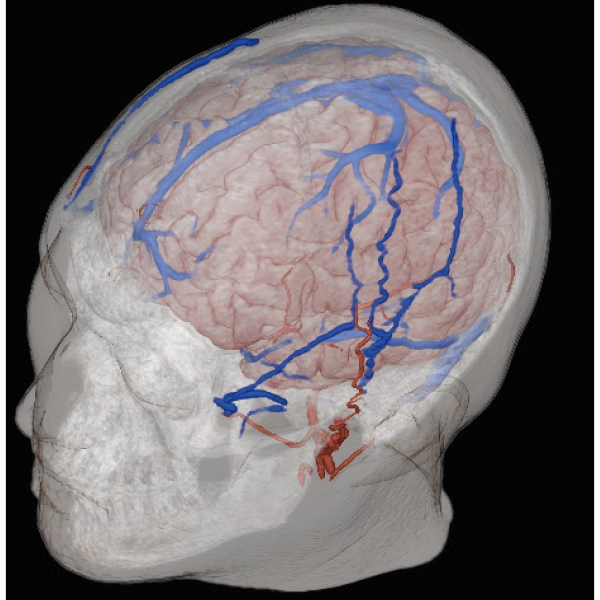

3DTOF MRA (MIP), 1:26

3D Balanced SARGE

with Phase Cycling,

0.93×0.70×1.0(0.5)mm, 1:44

3DTOF MRA RADAR (MIP)

3D MRCPA (MIP)

Lower extremity

non-contrast MRA (MIP)